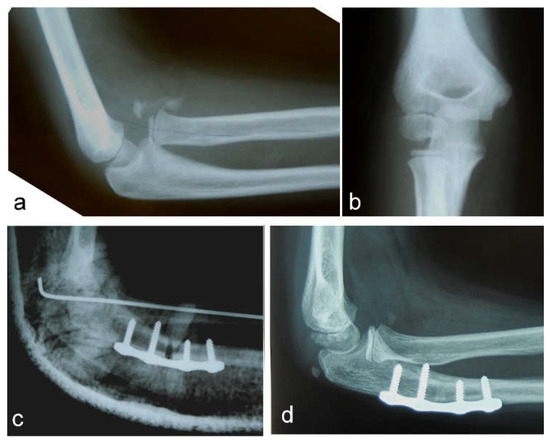

Figure 1. Neglected Monteggia fracture: (a) anterior dislocation of the radial head with heterotopic ossification visible on a lateral view; (b) AP view; (c) high posterior angulation and elongation osteotomy of the ulna stabilized with a plate and four screws. Transcapitellar fixation of the radial head with Kirschner wire; (d) the reduced radial head and healed ulnar osteotomy are visible on a lateral X-ray before removal of the plate and screws.